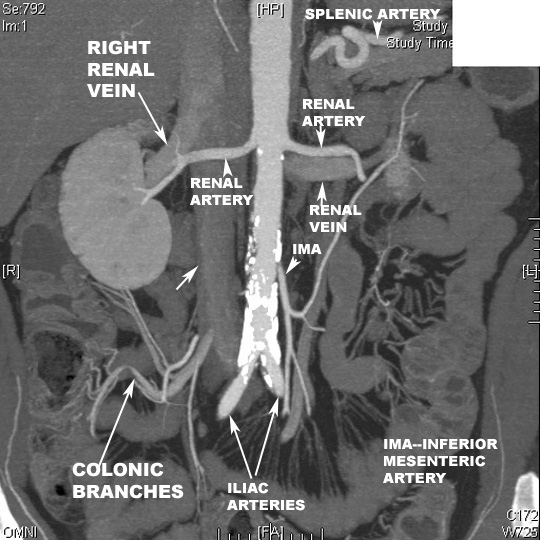

| PA view Reconstructed image | Origin and course of renal Arteries |

| PA view Reconstructed Image | Identify the branches of Abdominal Aorta |

| Lateral view Reconstructed Image | Identify the branches of Abdominal Aorta |